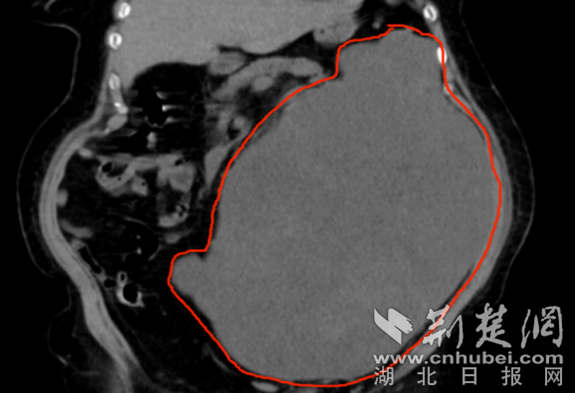

术前CT提示腹腔巨大肿瘤,占据大半个腹腔 通讯员 供图

74岁的李婆婆(化名)这2年发觉肚子越来越大了,一直以为是自己长胖,但近2个月老感觉自己肚子越来越涨,偶尔还有腹痛症状,大便也总是解不干净,肚子也大的越来越不正常,这才来到当地医院,刚做完腹部CT,就让门诊医师吓一跳,CT提示肿瘤已将占满大半个腹腔,但当地医院考虑到婆婆已74岁高龄以及腹膜后肿瘤手术风险极高,不敢贸然给李婆婆安排手术治疗。